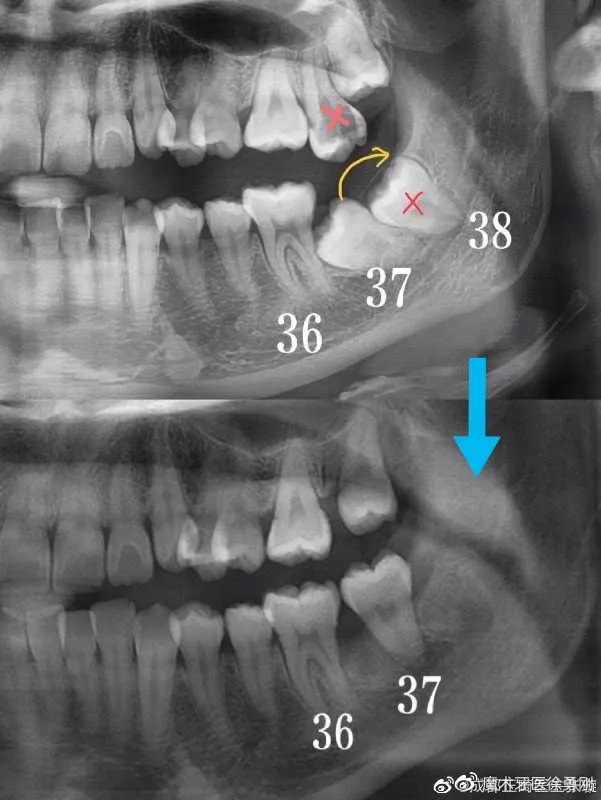

3,如果患者问题较多较重,如:非常规拔牙(因蛀牙拔了靠后的磨牙等),后牙区存在锁颌(一种严重的后牙区不良咬合),也会使治疗时间延长。

有些复杂的病例,多半都是出自正畸大师之手:

在微博上,有很多的正畸大师,经常分享一些复杂病例供同行们评价,赏心悦目。同时,也有不少正畸失败的患者在吐槽、指责Ta们的医生,而且我从微博、贴吧、百度里发现,有一些治疗失败的患者,她们追悔莫及、欲哭无泪的控诉,就跟那些深受“美容冠”伤害的人一样,明显发生了抑郁症倾向。这些失败病例的表现多种多样,有咬合错乱的,有前牙牙根暴露的,有颞颌关节紊乱的,而这些多数都缘于设计失误。